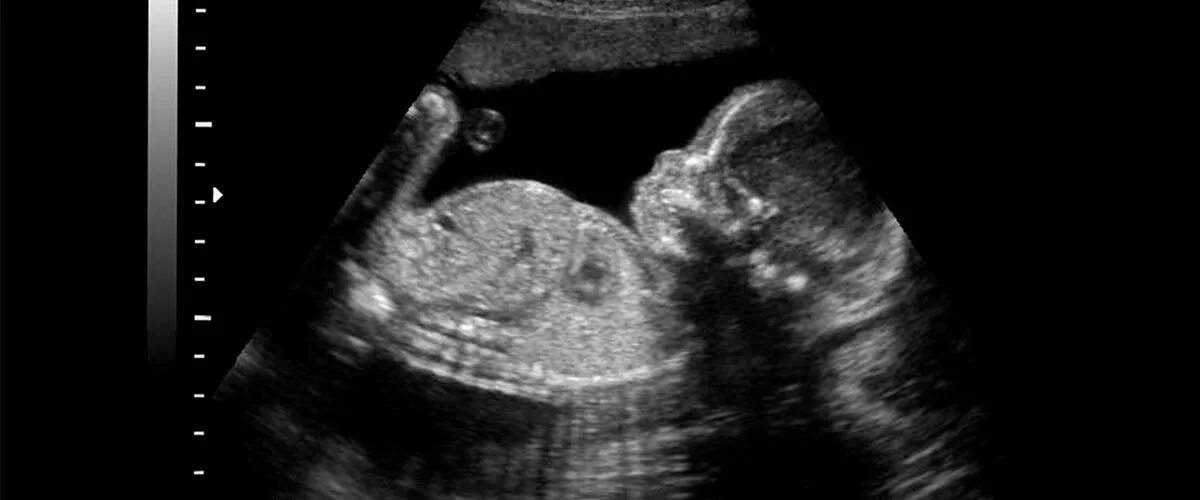

Скрининг 21 неделя